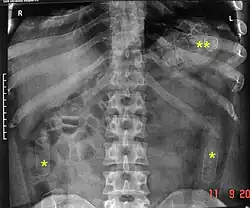

Plain radiograph of the abdomen of a drug "mule" showing swallowed drug capsules

Abdominal X-ray showing swallowed packages of cocaine.

Routine detection of the smuggled packets is extremely difficult, and many cases come to light because a packet has ruptured or because of intestinal obstruction. Unruptured packets may sometimes be detected by rectal or vaginal examination, but the only reliable way is by X-ray of the abdomen. Hashish appears denser than stool, cocaine is approximately the same density as stool, while heroin looks like air.[11][12]